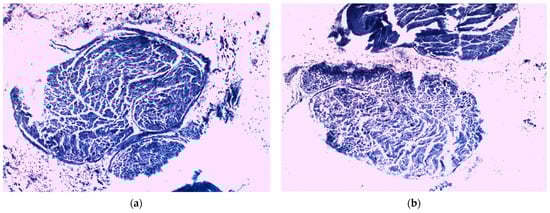

In the analysis of the right sciatic nerve samples from animals in both groups, the same differences were observed, in histological and especially in TEM analysis. Regarding the right sciatic nerve of the animals in the control group, multiple myelin sheath disorganization sites were noticed (Figure 10a and Figure 11a,b), which are in fact disorganizations of the plasmalemma extensions of Schwann cells that surround the axons. The loss of axonal myelin layers’ continuity could be described as ovoid shaped areas of rarefaction (inset of Figure 11b), which induced a degeneration of the axon into debridements that followed the original endoneural tube. These changes in the compaction of the myelin sheath could be associated with a low expression of transmembrane myelin-specific proteins that are involved in its compaction. As a result, hypomyelination or demyelination occurred and, therefore, it resulted into a poor nerve recovery. These findings correlated with what the studied revealed about the evolution of the control group from the perspective of the SFI score, pain level, and body weight.

Figure 10.

Right sciatic nerve samples—histological studies. (a) Control group nerve sample; (b) CMNPs treatment group nerve sample.

In comparison with the control group, the right sciatic nerve of the animals that received CMNPs treatment had almost normal morphology with discrete to moderate internal disorganization (Figure 10b and Figure 11c,d). The frequency of the ovoid areas of myelin disorganization was suggestively lower than in the control group. Moreover, TEM images observed the nanoparticles mostly at the axon and myelin sheath level as small black oval shape dots.